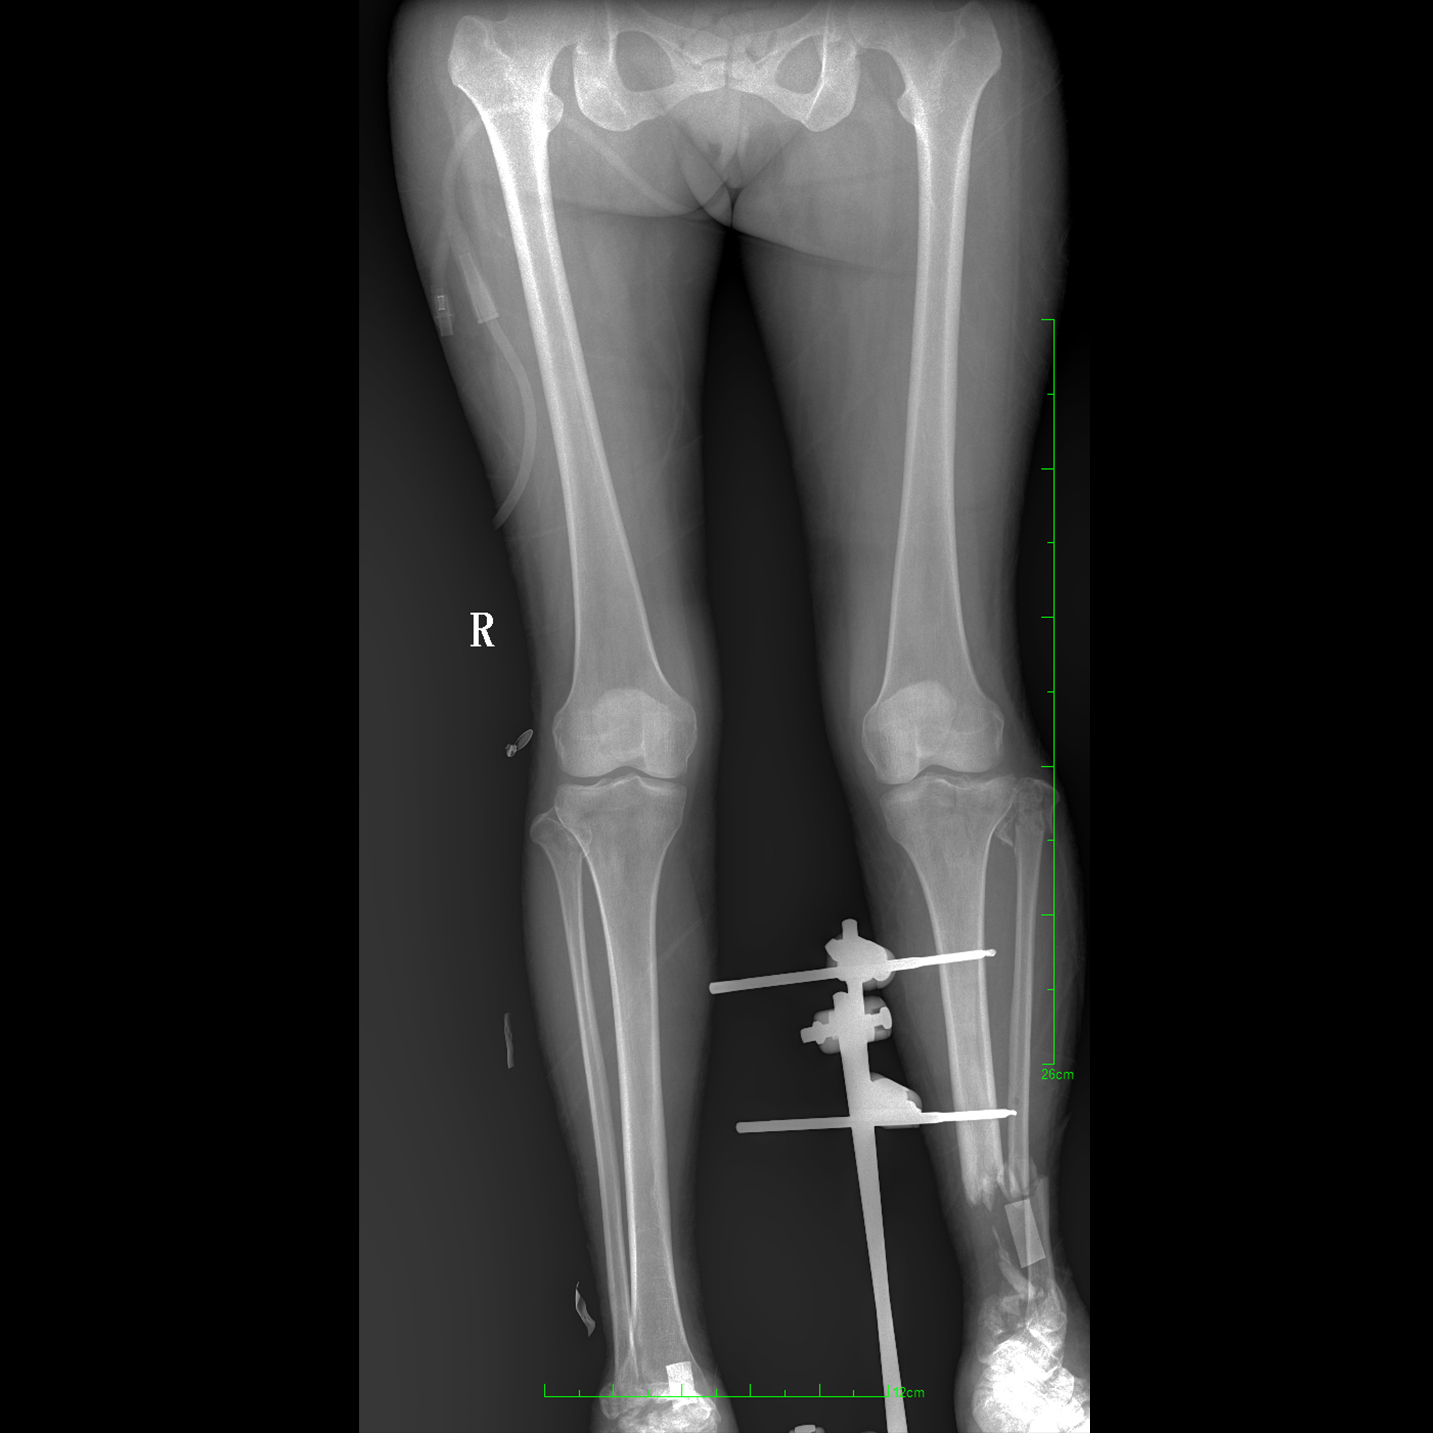

支持全脊柱攝影、雙下肢攝影、脊髓造影、復雜創(chuàng)傷、人工關(guān)節(jié)置換、關(guān)節(jié)損傷的修復重建等大視野臨床應用

17"*34"有效視野,一次成像不拼接。相較于多張攝影再軟件拼接的DR設備,PLX8600解決了拼接圖像存在密度不均勻,拼接處圖像配準和放大效應等問題,給臨床帶來了大視野影像解決方案,可一次性覆蓋全脊柱或雙下肢影像。

除常規(guī)靜態(tài)攝影外,PLX8600大平板具備動態(tài)透視和點片功能,透視采集功能可支持大視野、多角度的可視化觀察。通過可視化的動態(tài)影像,配合點片功能,能夠很好的觀察復雜部位病灶,有效的抓取關(guān)鍵幀,降低患者多次攝片的概率。如:全脊柱狀態(tài)評估、長骨關(guān)節(jié)活動度、下肢靜脈造影瓣膜功能評估、消化道功能評估、脊髓造影等更多大視野臨床應用。